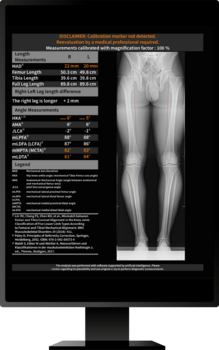

The underlying technology of ImageBiopsy Lab's software is based on machine learning. This means that computers learn from examples of previous cases. Thousands of X-ray images, manually marked by doctors, serve as training data: they point out to the software where joint spaces, bone angles, or fractures are located. The system learns to automatically recognize and measure similar structures in new images. ImageBiopsy Lab's solutions recognize relevant structures in seconds, measure defined parameters, and generate a structured analysis report – standardized and reproducible. This creates a reliable basis for diagnostics, follow-up care, and therapy decisions.

Today, ImageBiopsy Lab has seven certified modules (MDR/TÜV SÜD, partly also certified by the US FDA) on the market. They address key anatomical regions such as the knee, hip, spine, and foot, and provide standardized analysis reports that are used in radiology and orthopedic clinics in Germany, Austria, and Switzerland. Installed on-premise, they run in the background and deliver additional information directly to the image.